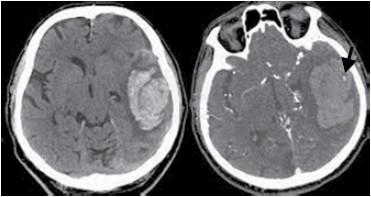

A tomografia de crânio a seguir corresponde a um paciente de 65 anos e hipertenso, admitido no pronto-socorro com crises convulsivas. Assinale a alternativa correta a respeito do local apontado pela seta na imagem.

(Arquivo pessoal; imagem usada com autorização)